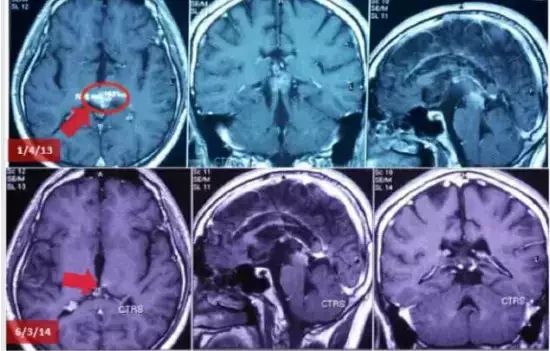

患者男性,22岁,诊断为松果体瘤,侵犯丘脑:肿瘤位于中脑(松果体区域)压迫丘脑(MRI 2012年11月23日),导致患者视力受损和严重头痛。

ECCT治疗4月后,肿瘤体积逐渐缩小(MRI 2013年1月4日),患者症状持续改善。治疗15月后,MRI示肿瘤几乎消失(2014年3月6日),患者状况几乎回复正常。在这个病例里,肿瘤通过脑脊液流出道与第四脑室相连,因此死亡细胞可完全清除。单纯使用ECCT而不用手术有望完全消除整个肿瘤。